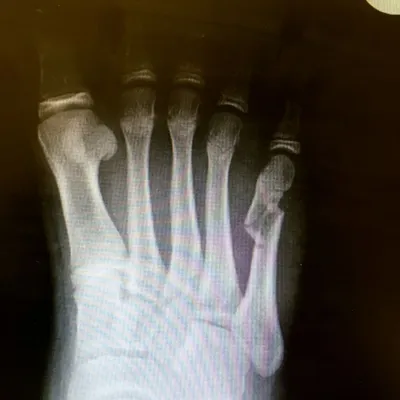

Pre and Postop ORIF Displaced Big Toe Intra-articular Pediatric Fracture (Below)

This is post-operative x-ray of a repair of a fracture of the long bone of foot connected to the great toe, There are three pins holding the fracture fragments in place, and once this heals the pins are removed.